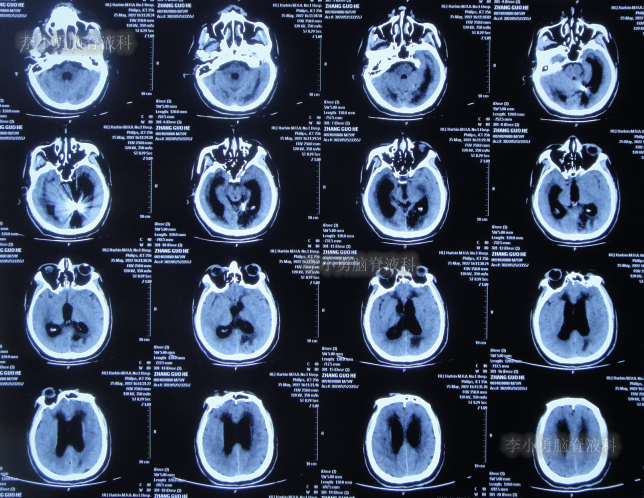

2022年4月27日(入院治疗3天),脑脊液培养出细菌,给予抗感染治疗,查头颅CT示脑室扩张加重(图-5)。

图-5:2022年4月27日头颅CT

抗感染治疗28天即2022年5月25日,查头颅CT示仍脑积水(图-6),脑脊液仍有细菌。

图-6:2022年5月25日头颅CT

抗感染治疗41天即2022年6月7日,脑脊液化验细菌消失,但查头颅CT示仍脑积水(图-7)。

图-7:2022年6月7日头颅CT